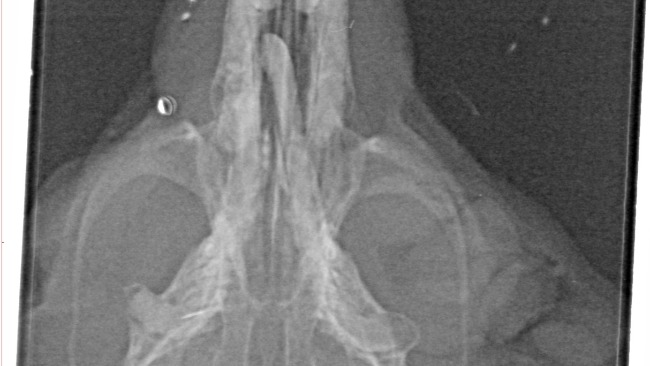

Badanie z 19 marca: USG wykazało dużego guza wychodzącego z macicy oraz obecność torbieli.

Dzisiejsze badanie w innej lecznicy (bez narkozy ze wzgledu na zwiększone ryzyko): Według opisu lekarza, żaden guz od macicy nie odchodzi. Torbiele są. Najbardziej niepokojące jest zaś nienaturalne wybrzuszenie ściany żołądka (w pobliżu okolicy gdzie miał być ten guz). Z nerkami na szczęście w porządku.

Mamy więc dwa zupełnie sprzeczne obrazy medyczne. Zamiast jasnych odpowiedzi, mamy jeszcze więcej pytań. O co chodzi? Co tam się właściwie dzieje?

W załączeniu zdjęcie dzielnej pacjentki podczas badania.